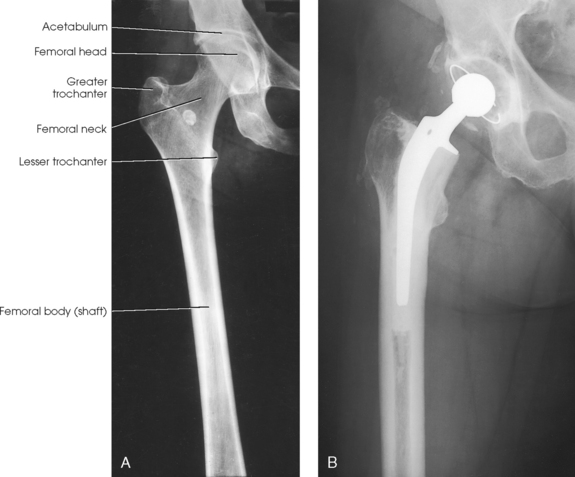

If the femoral heads are separated by an unusually broad pelvis, the bodies (shafts) are more strongly angled toward the midline.

• Center the affected thigh to the midline of the IR. When the patient is too tall to include the entire femur, include the joint closest to the area of interest on one image (Fig. 6-164).

• For projection of the distal femur, rotate the patient’s limb internally to place it in true anatomic position. The limb is naturally turned externally when laying on the table. Ensure that the epicondyles are parallel with the IR.

• Place the bottom of the IR 2 inches (5 cm) below the knee joint.

Structures shown: The resulting image shows an AP projection of the femur, including the knee joint or hip or both (Figs. 6-165 and 6-166).